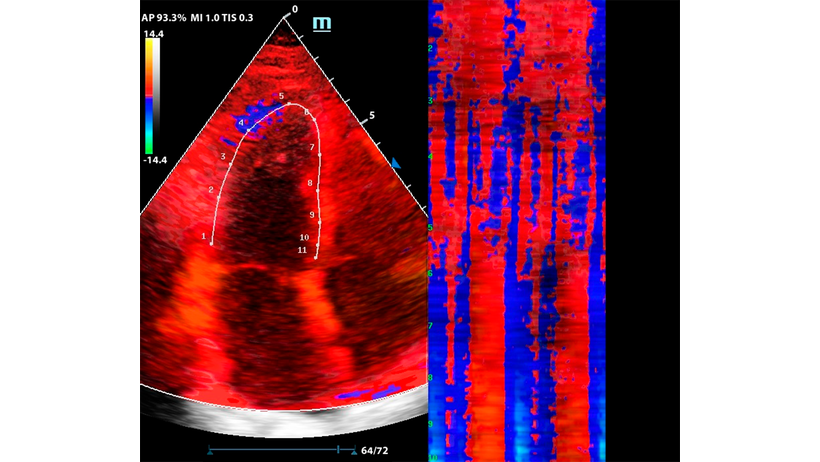

Функция изогнутого М-режима особенно интересна в комбинации с тканевым допплером (TDI). Оконтуривание миокарда в цветовой карте TDI позволяет оценить кинетику левого желудочка посегментно, в виде цветовой карты на графике Free Xros CM.

Метод разворачивает левый желудочек в плоскую палитру движений за счет окраски тканевого допплера, это позволяет сравнить кинетику в каждом моменте цикла сокращения и расслабления.